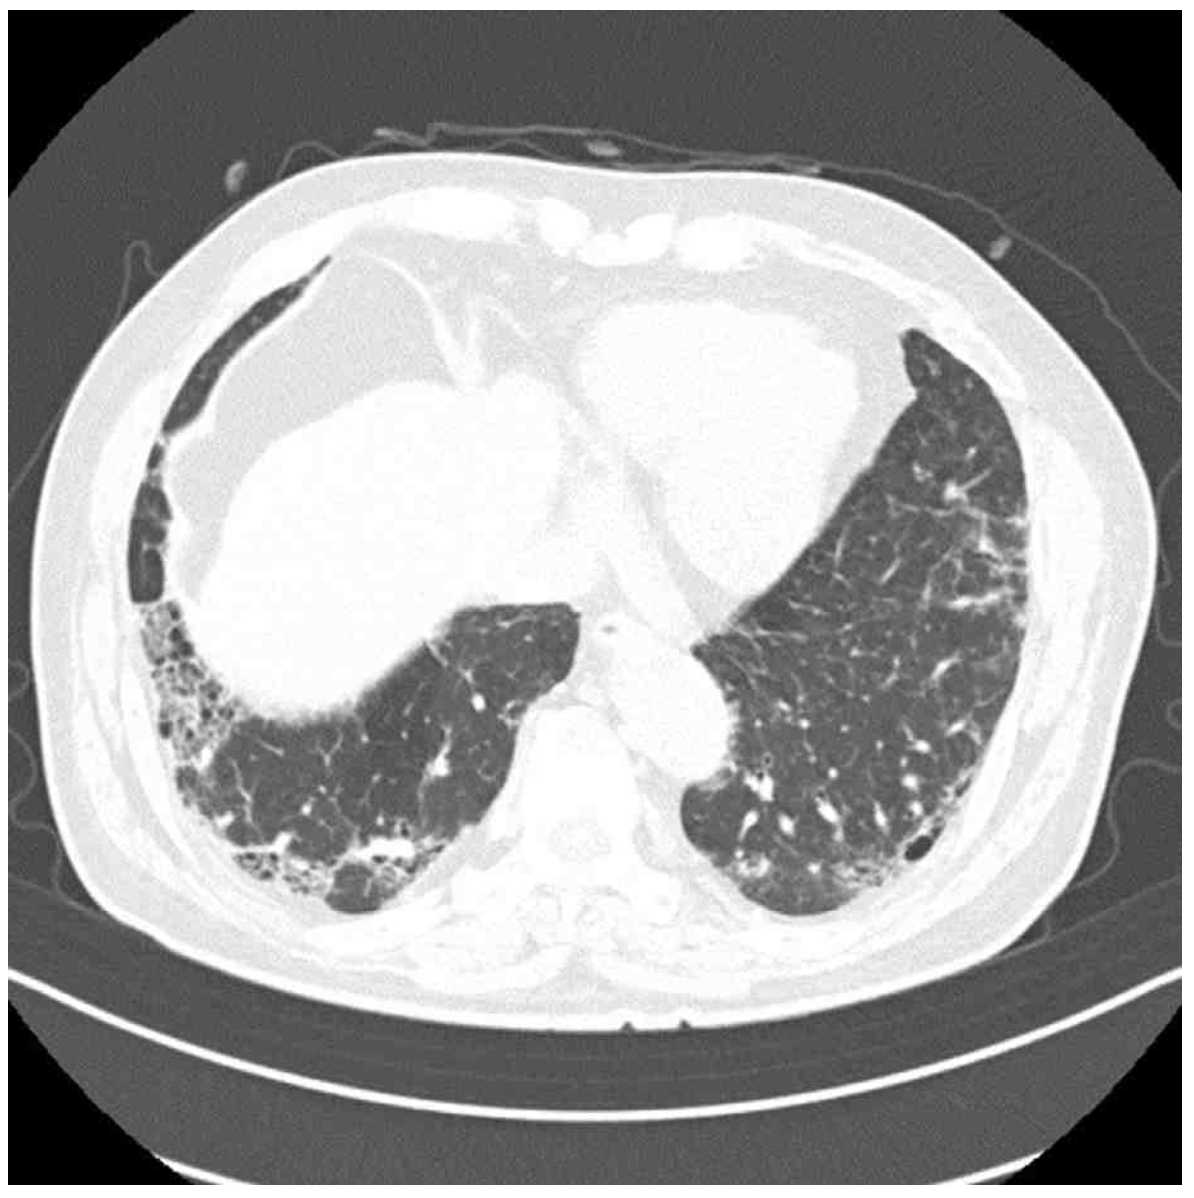

CT: Basal-predominant reticulation, GGO

CXR상 양측 폐야에 증가된 opacity가 관찰되며, 더 자세한 평가를 위해 실시한 chest CT상 basal-predominant reticulation, mild honeycombing 및 GGO가 관찰되므로 간질성 폐질환(ILD)이 강하게 의심된다.